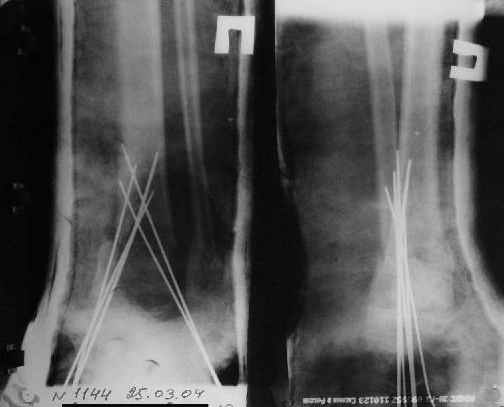

A>> Спицы удалены через 1,5 недели после операции.

A>> Особого смысла в них не было.

AVM> Не было. Можно было, если особенно хотелось, провести одну

AVM> интрамедулярно...

Но только смысла не имело. Подвижности небыло. Рубцы хорошо держат.

Так как речь зашла непосредственно о травме, см этапные

снимки. Как все было

Фиксация

в гипсе